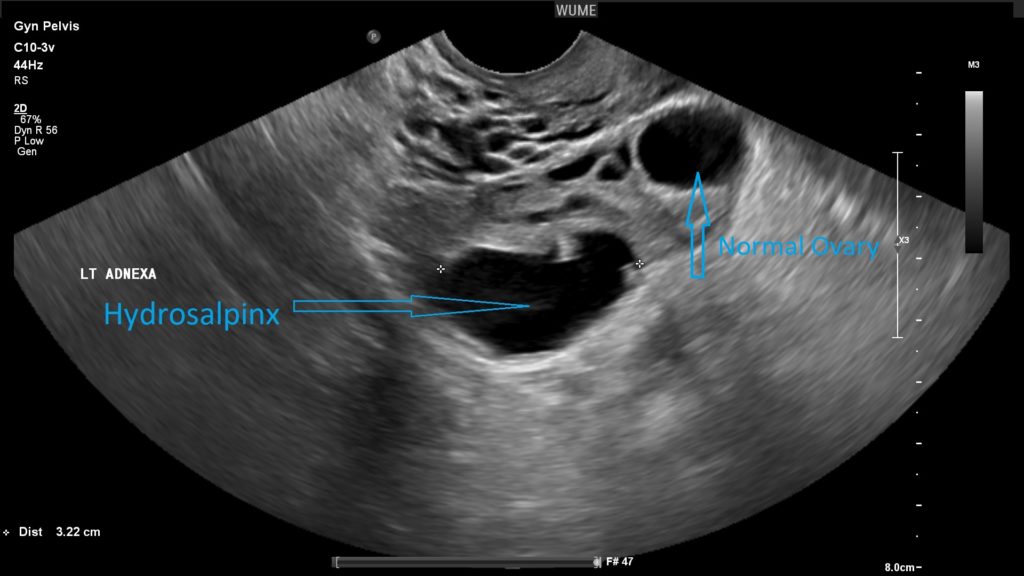

هیدروسالپینکس

Hydrosalpinx به معنای مایع در لوله فالوپ است. این یک یافته رایج در زنان مسن و زنان با مشکلات باروری است. این را می توان با سونوگرافی لگن تشخیص داد.